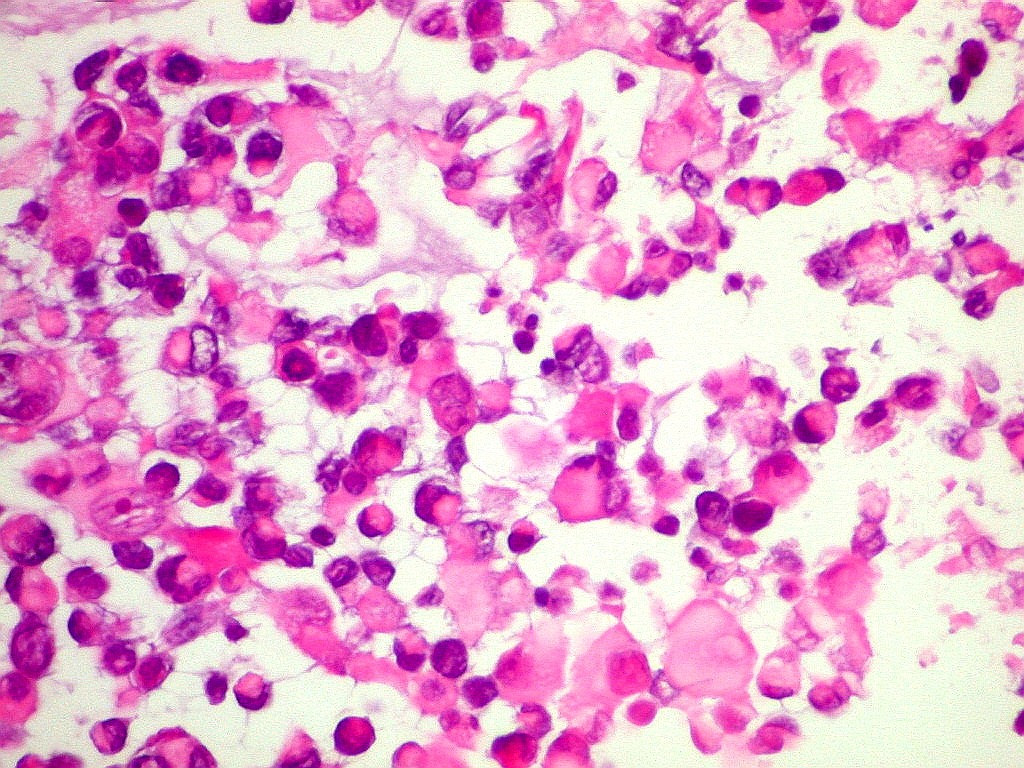

INI1.

Antígeno nuclear presente em todas as células normais.

Sua ausência é importante marcador do tumor teratóide

rabdóide atípico (metade direita do campo). Na metade

esquerda, vaso com células positivas. Os vasos não

pertencem ao tumor, mas o invadem a partir dos tecidos infiltrados. |